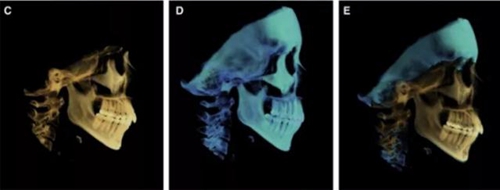

治療后數(shù)據(jù)提示治療目標(biāo)達(dá)成。面相結(jié)果提示微笑及側(cè)貌得到改善(圖6)。達(dá)到了安氏I類尖牙關(guān)系和安氏II類磨牙關(guān)系,形成尖牙保護(hù)合。牙齒中線無偏斜,達(dá)到理想的覆合覆蓋,Spee曲線得到整平。

治療后全景片提示間隙得到關(guān)閉,除了左下頜第一前磨牙外牙根平行度可,無明顯骨及牙根吸收。(圖7)

治療后頭側(cè)數(shù)據(jù)提示:無明顯骨性變化(上頜SNA82.1°,下頜SNB74.9°),上頜前牙得到內(nèi)收,略舌傾,頦部前后位置無明顯改變,仍未凸面型(圖8,表)。將治療前后圖像重疊后結(jié)果如(圖8及圖9),24月后隨訪結(jié)果見圖10.